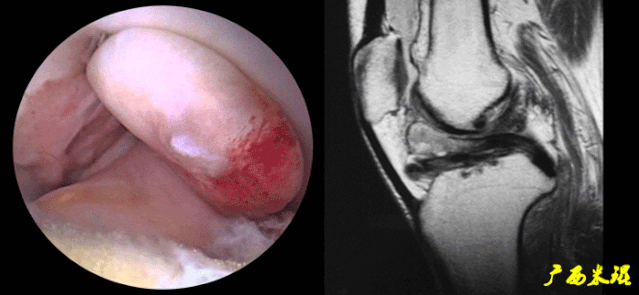

(七)ACL损伤直接征象

1)ACL本身的形态和信号异常:

2)不连续:

-

有韧带的低信号,但中断不连续。

一般见于新鲜损伤。

6)假瘤:

韧带损伤后断端较整齐,残端组织增生并被滑膜包裹呈“瘤状”,如果突出于前方为“独眼征”。

多见于韧带股骨附着部撕裂及部分撕裂。